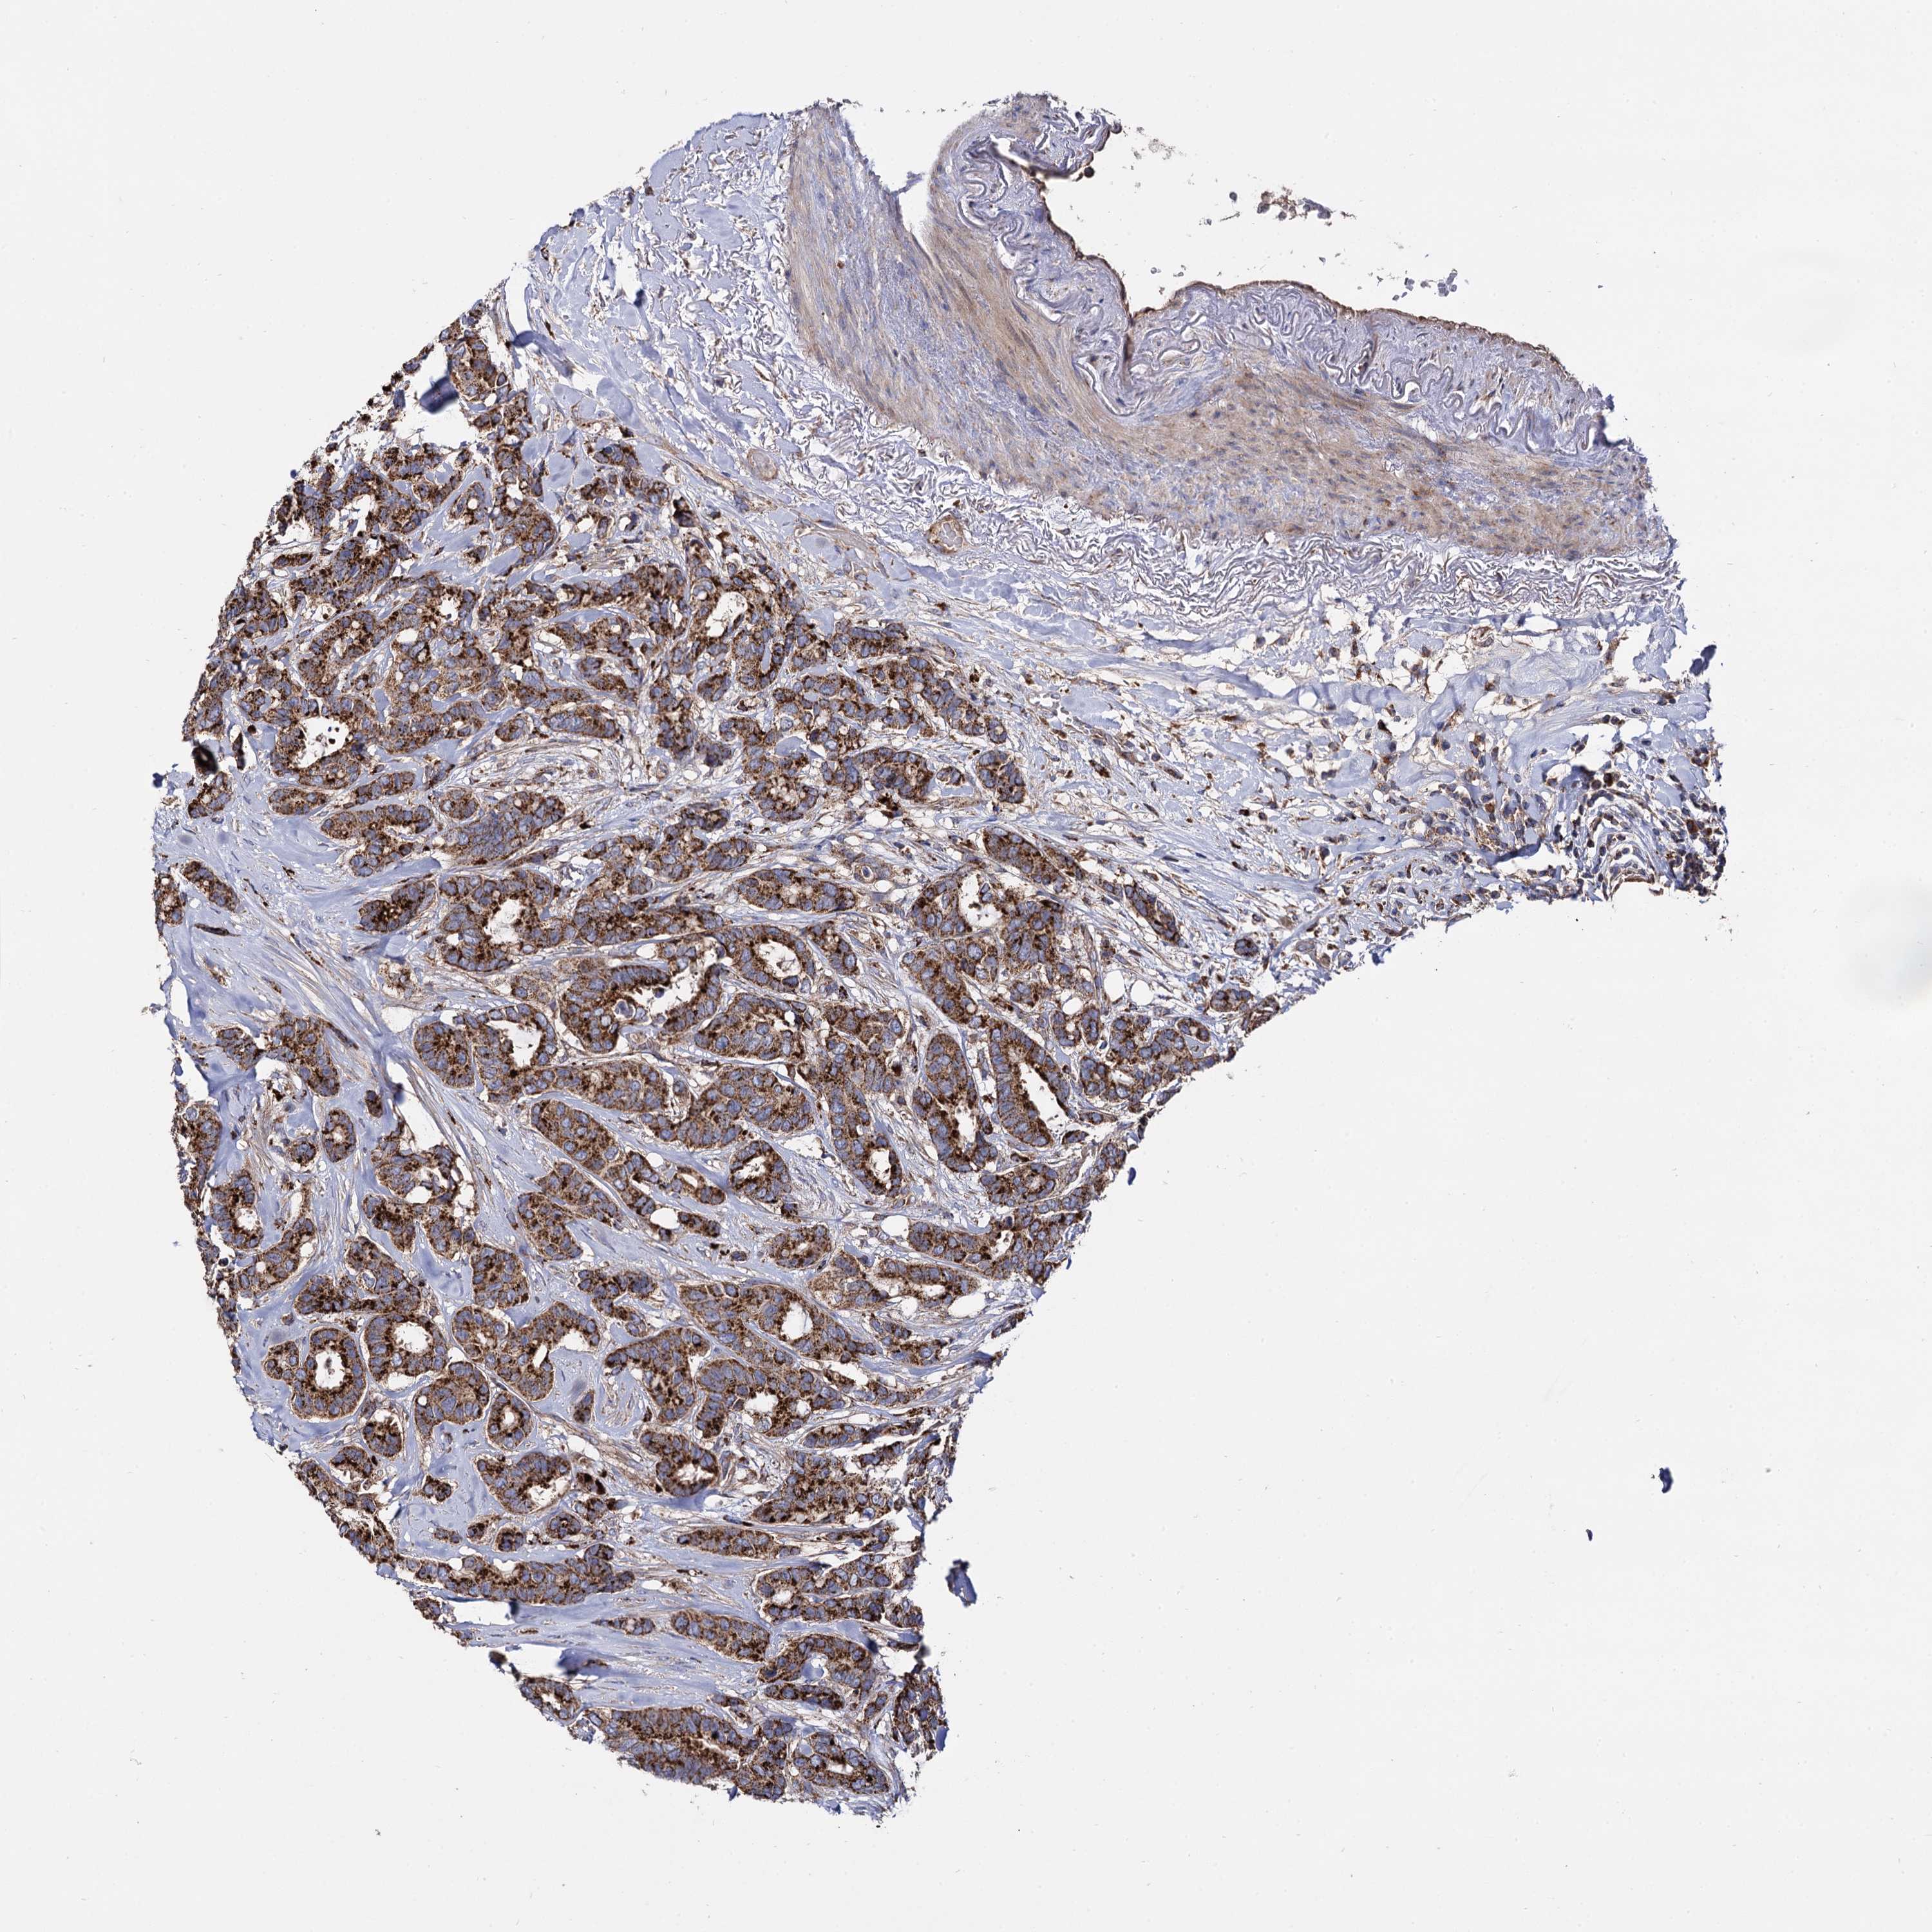

CANCER BREAST CANCER Show tissue menu

BRCA TCGA BRCA VALIDATION PROTEIN EXPRESSION

ANTIBODIES

AND

VALIDATION